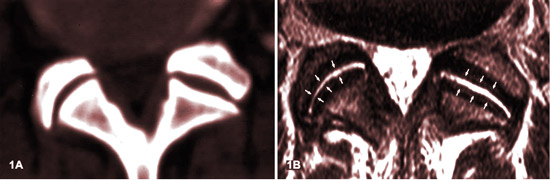

ARTHROSE FACETTAIRE (spondylarthrose) ET SON APPARENCE IRM :

LES STADES

Source: MR imaging and CT in osteoarthritis of the lumbar facet joints.